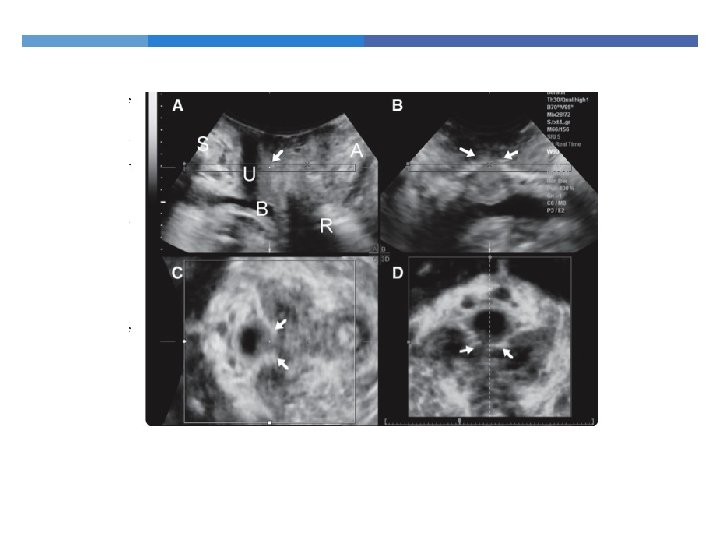

Endoanal Ultrasonography 360 degree rotating probe Simple and relatively painless Excellent visualization of the 5 layers of the anal canal

Endoanal Ultrasonography Muscle thickness Scarring Loss of muscle tissue

Endoanal Ultrasonography